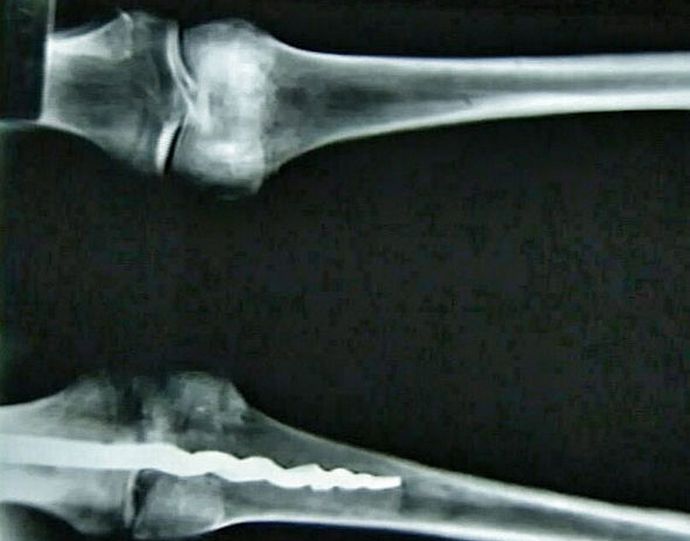

valokuva avoimen lähdekoodin ryhmä amerikkalaisia tutkijoita DNA-analyysi egyptiläisestä muumiosta, joka löydettiin hänen ruumiistaan todellinen ortopedinen tappi, joka ei ole huonompi muotoilu modernit kollegansa. Ainutlaatuinen löytöpituus 23 senttimetriä, hän oli metallia, ja hänen suunnittelunsa on erilainen silmiinpistävä samankaltainen kuin vuonna 1997 käytetyissä ortopedisissa nastoissa lääke tänään.

Asiantuntijoiden mukaan miehen polvessa ovat muinaiset kirurgit laita nasta kiinnittämällä luut kiinnittämällä se orgaaninen hartsi. He tekivät sen niin taitavasti ja ammattimaisesti, että monimutkaisin toimenpide ei jättänyt jälkeäkään potilaan kehossa. Päätellen löydettyä löytöä, menetelmiä, joita lääkärit ovat käyttäneet nykyajan lääketieteessä, ovat olleet jo kauan tunnettu esivanhempiemme kanssa ja he ovat onnistuneesti soveltaneet niitä käytännössä.

Vielä ei tiedetä, kuka tarkalleen oli egyptiläinen, polvessa joka löydettiin uskomaton tappi. Yhdysvaltain tutkijat Brigham Youngin yliopisto näki hänet melko vahingossa röntgenkuvat, ja sitten poistetaan kehosta, hieman yllättynyt sen löytö.

Löytynyt muumio on vähintään 3000 vuotta vanha, mikä tarkoittaa, että silloinkin muinaisilla egyptiläisillä oli tarvittava tieto rakentamiseksi nastat, jotka pystyvät kiinnittämään siirretyt luut oikein asema ja suorittaa monimutkaisia kirurgisia toimenpiteitä.

Tutkijat eivät voi vielä selittää salaperäisen löytön luonnetta, muutti ideoitaan muinaisesta lääketieteestä. Wilfred Griggs, johtaa tutkimusryhmää, jonka käsissä se osoittautui ainutlaatuinen muumio, vakuuttunut siitä, ettei hän antaisi paljon yhdelle selvittää tarkalleen, kuinka egyptiläiset lääkärit onnistuivat luomaan ja sijoittamaan sinne miehen vartalo on niin moderni nasta.